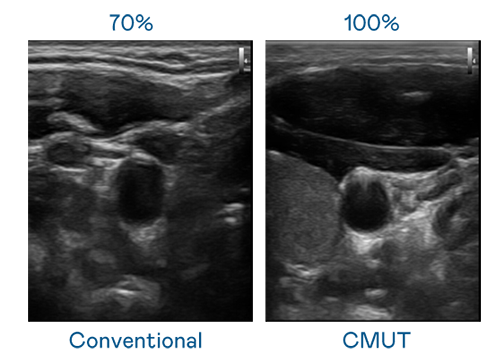

CMUT 技术是一种用电容式微机电元件来产生超音波讯号的技术。与传统 PZT 压电式技术相比,CMUT 频宽增加 30%,更宽频的超音波讯号让影像解析度大幅提升,是实现高影像品质医疗超音波扫描、促进精准医疗发展的关键技术。

大频宽带来超清晰影像

超音波影像的解析度高低,首先取决于探头能发出的讯号频宽。小勐拉99厅 CMUT 可提供高清晰的超音波讯号,提供高频宽、高灵敏度、影像纹理细节更高的超音波影像,协助医护人员缩短影像判读时间及利用精准的医疗影像进行诊断。